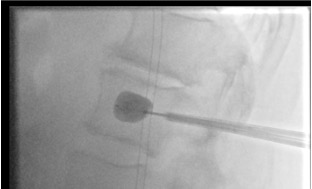

Balloon inflation — height restoration

- Target position: Balloon placed in the central/anterior trabecular bone, posterior to the anterior cortex, anterior to the posterior wall

- Balloon inflation compacts trabecular bone radially and cranio-caudally, reducing the fracture and creating a defined cavity

- Cavity volume correlates with expected cement volume — do not overfill the cavity with cement